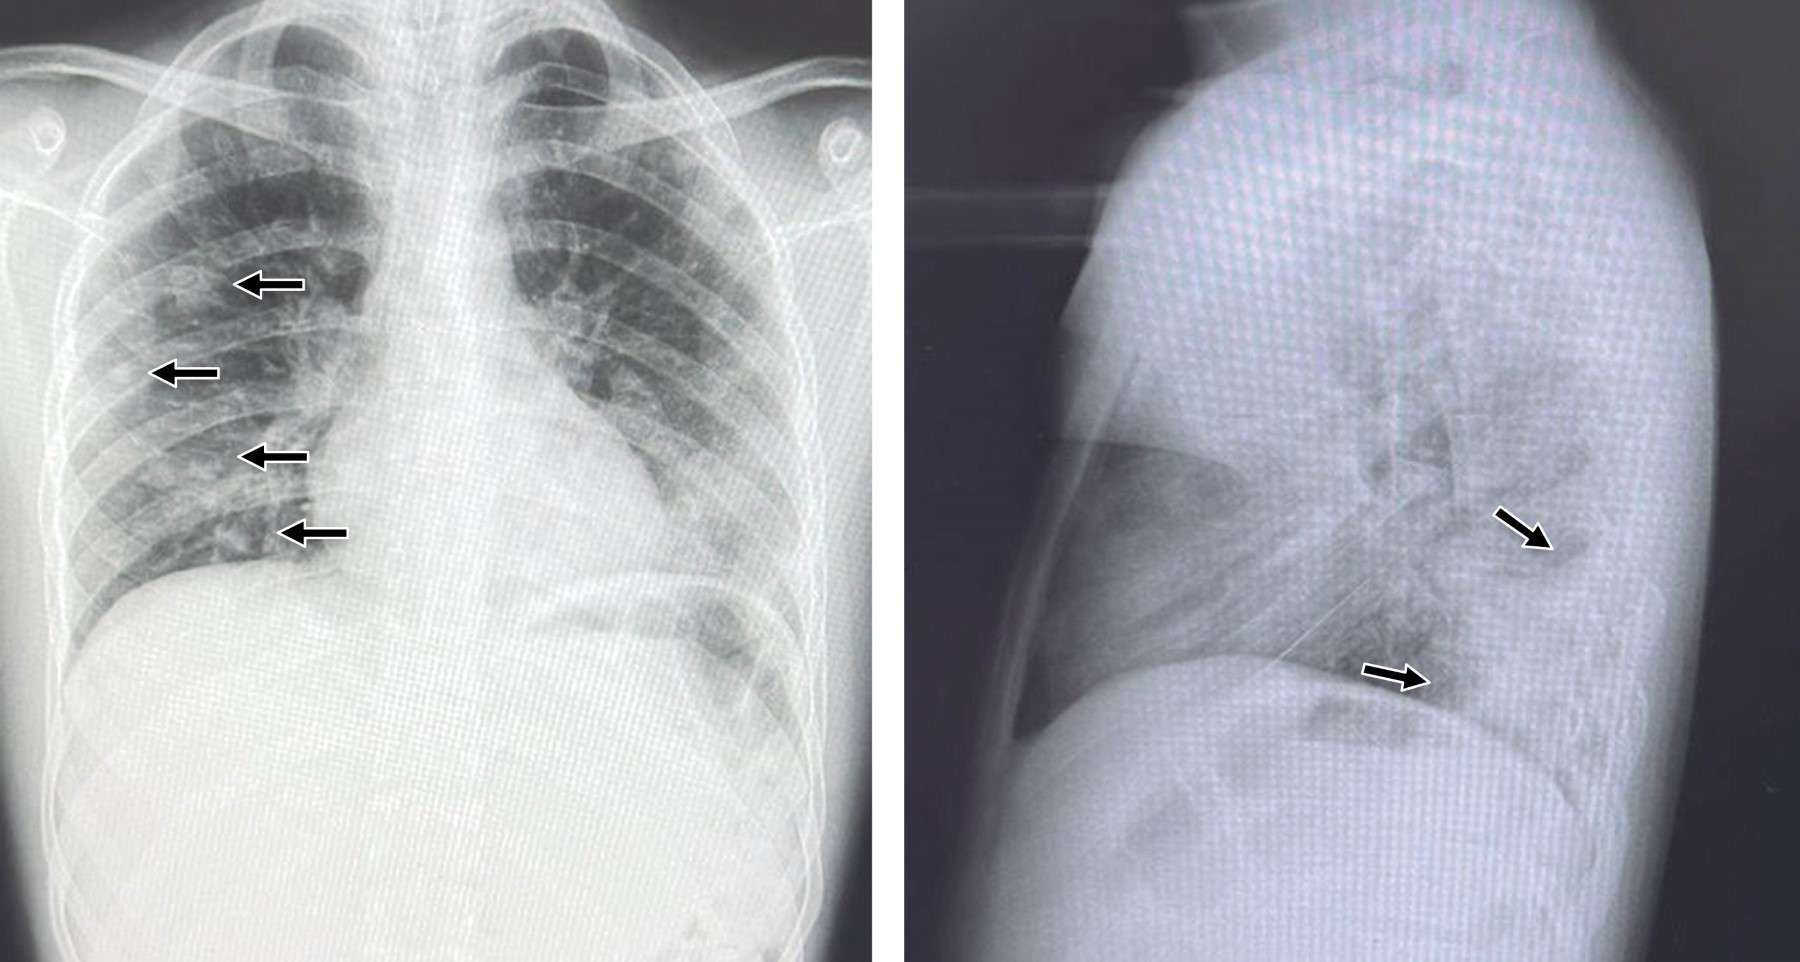

Introducción: Staphylococcus aureus es un agente causal común de infecciones de piel y tejidos blandos en la población pediátrica. Sin embargo, puede provocar enfermedades invasivas como infecciones osteoarticulares, neumonía y bacteriemia. Este caso clínico describe la progresión de una infección cutánea superficial en un adolescente que evolucionó a una afección invasiva grave. Presentación del caso: paciente de 16 años, previamente sano, quien presentó una lesión cutánea en la región cervical. En cuestión de días, la infección progresó rápidamente, provocando fiebre, malestar general y síntomas sistémicos. Los hemocultivos confirmaron la presencia de S. aureus resistente a la meticilina, y los estudios de imagen revelaron émbolos pulmonares. Se inició tratamiento con antibióticos de amplio espectro, ajustados según las pruebas de sensibilidad. Se observó mejoría clínica y el paciente fue dado de alta sin complicaciones. Conclusión: este caso destaca la posibilidad de que en pacientes pediátricos con infección cutánea por S. aureus progresen a una enfermedad invasiva potencialmente mortal. Por lo que es importante su reconocimiento y el tratamiento apropiados para prevenir complicaciones graves.

Figura 1

Figura 2